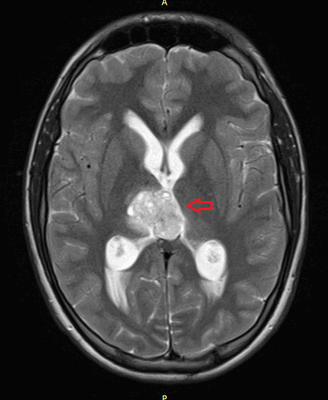

Головной мозг

Герминогенные новообразования в данной области - это примерно 2-4% от всех внутричерепных (интракраниальных). Патология в 75% случаев диагностируется у мальчиков, за исключением турецкого седла, где новообразования в основном локализуются у девочек.

Герминомы формируют инфильтрирующие опухоли больших размеров, часто являющиеся источниками субарахноидальных (между мягкой и паутинной оболочками мозга) и вентрикулярных (желудочковых) метастаз.

Рисунок 7. - Герминома головного мозга.

- КТ (расшифровка: компьютерная томография), МРТ (расшифровка: магнитно-резонансная томография), ПЭТ-КТ (расшифровка: позитронно-эмиссионная томография, совмещенная с КТ). Эти обследования необходимы, чтобы рассмотреть структуры организма послойно и визуализировать опухоль. Они показывают, как сильно распространен патологический опухолевый процесс на находящиеся рядом ткани и органы, есть ли поражение костей. КТ - это самый чувствительный метод для обнаружения метастазов в легких. Проведение МРТ и КТ головного мозга необходимо, чтобы обнаружить и визуализировать герминогенные новообразования эпифиза.

Рисунок 9. - метастаз в головной мозг при герминогенной опухоли.